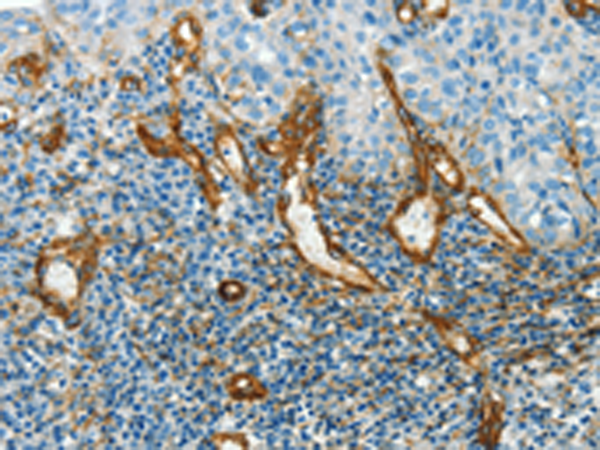

分类: 科研抗体货号: P04642别名: F6PK; HL2K; PFRX应用: IHC反应种属: Human, Mouse, Rat